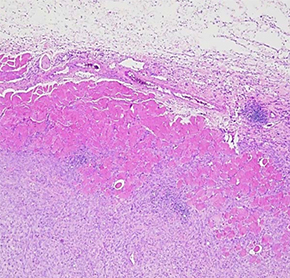

肿瘤检体经过病理染色与医师判读后,确定肿瘤的类型、分级与分期,拟出适合的治疗方案与用药组合。

· 实验室人员进行标准病理染色程序